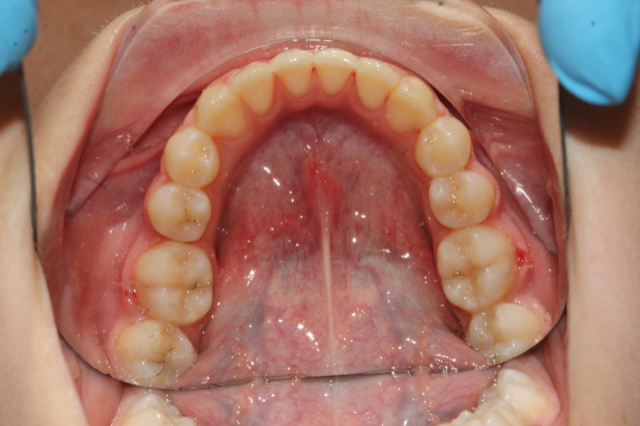

Felső fogsor szabályozás

A páciens felső metszőfogai erősen torlódtak, ami esztétikai és funkcionális problémát okozott. A kezelés után harmonikus, szabályos fogív alakult ki.

Felso-fogsor-szabalyozas-elott